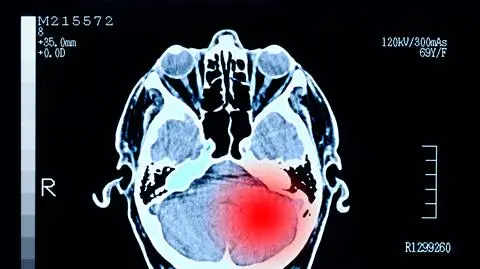

38-latek z dnia na dzień stał się bardziej zmęczony, napalony i agresywny. Dodatkowo stracił węch i smak. Jak się okazało, mężczyzna cierpiał na guza mózgu. - Szczerze mówiąc, kiedy się dowiedziałem, nie mogłem w to uwierzyć - powiedział.

Guz wielkości pomarańczy

Jak się okazało mężczyzna miał w mózgu guza, wielkości pomarańczy, który był przyczyną tak nagłej zmiany charakteru.

Nowotwory te mogą wywoływać zmiany osobowości, zwłaszcza jeśli znajdują się w płacie czołowym, który reguluje osobowość i emocje. Sygnały, które powinny budzić niepokój to przede wszystkim: drażliwość, agresja, dezorientacja i zapominanie, a także wahania nastroju oraz brak zainteresowania i motywacji.